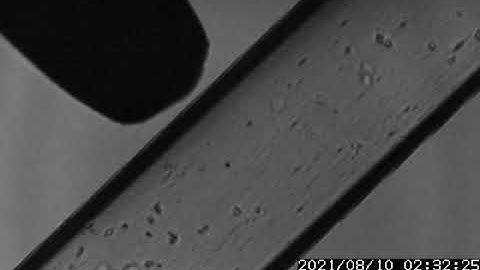

Microbubble Cavitation - Low Output Power